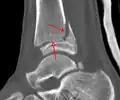

Une fracture triplane de la cheville vue sur une radiographie standard

Une fracture triplane de la cheville vue par TDM